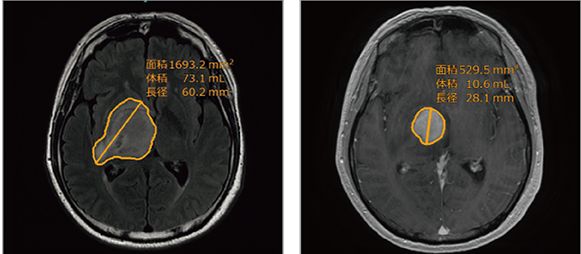

ユーザーが指定した神経膠腫(グリオーマ)疑いのある領域内のVOI抽出します。本機能は2点指定のVOIに含まれます。